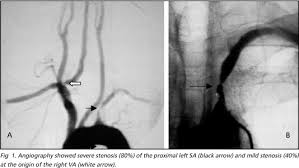

Right subclavian steal syndrome. Although a low-grade stenosis is usually asymptomatic and may remain unobserved a. Report of 3 Cases and Literature Review. In patients with the subclavian steal syndrome occlusion of the subclavian artery or innominate artery proximal to the vertebral artery on that side gives rise to a pressure differential between the two vertebral arteries.

The term subclavian steal describes retrograde blood flow in the vertebral artery associated with proximal ipsilateral subclavian artery stenosis or occlusion usually in the setting of subclavian artery occlusion or stenosis proximal to the origin of the vertebral artery. Subclavian artery stenosis is an uncommon vascular disease showing a 4-fold left rather than right-sided predisposition. Symptoms of SSS include vertigo during arm exertion and hand or arm pain and numbness or weakness in the arm involved due to hypoperfusion.

Subclavian steal syndrome SSS is a condition secondary to an occlusion in the proximal subclavian artery which leads to upper-extremity blood supply to be derived by reversal of flow within the ipsilateral VA. Primary Stenting of Right-Sided Subclavian Artery Stenosis Presenting as Subclavian Steal Syndrome. Blood is drawn from the collateral circulation which results in reversed blood flow in the ipsilateral vertebral artery. The term subclavian steal describes retrograde blood flow in the vertebral artery associated with proximal ipsilateral subclavian artery stenosis or occlusion usually in the setting of subclavian artery occlusion or stenosis proximal to the origin of the vertebral artery. The subclavian steal syndrome is a condition where hypoperfusion of the cerebrovascular system is caused by occlusion or severe obstruction of the proximal subclavian or brachocephalic artery. Alternatively innominate artery disease has also been associated with. Although a low-grade stenosis is usually asymptomatic and may remain unobserved a. The term subclavian steal was coined by Fisher as the reversed retrograde ipsilateral vertebral blood flow was due to the stealing of blood from the posterior cerebral circulation by the subclavian artery. Since recognition of this syndrome can lead to successful treatment a review by.